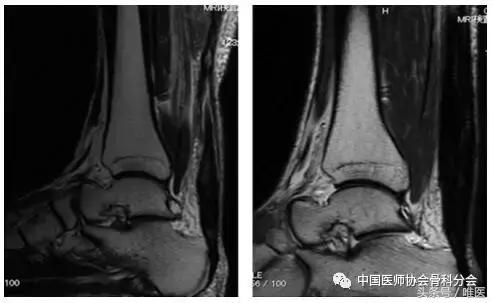

在术前T2加权图像中,在22例患者中观察到肌腱状肌腱增厚和腱内弥漫性高信号改变,但这些患者术后6个月MRI在MRI腱上有均匀的低信号改变(图3)。在其余8名患者中观察到肌腱变薄。在这8例患者中的6例中,术前观察到弥漫性腱内高信号变化。但术后6个月在MRI中可见肌腱形腱增厚和均质的低信号改变(图4)。

图3:一个34岁女性肌腱的T2加权磁共振成像显示梭形肌腱增厚。左:术前图像显示损伤后4个月的弥漫性腱内高信号改变。右:术后6个月图像显示均匀的低信号改变。

图4:一个63岁男性肌腱的T2加权MR图像。左:术前图像显示损伤后3个月的腱变薄和弥漫性腱内高信号改变。右:术后6个月时显示梭形肌腱增厚和均匀的低信号改变。